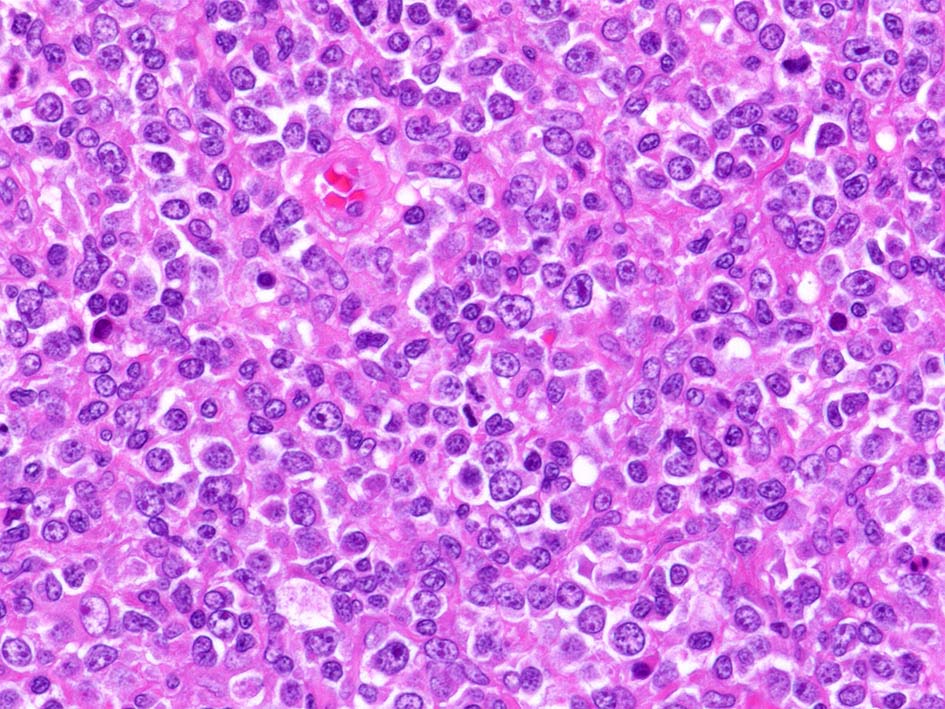

腫瘍内に壊死が認められる. 異型リンパ球の密な増殖により精細管は消失している.

腫瘍細胞はcentroblastic cells. mitosisやapoptosisが多い.